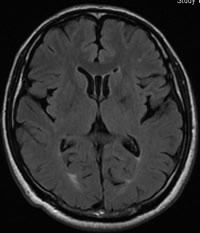

| FLAIR画像(フレア) | 主に病変を目立たせる撮り方 |